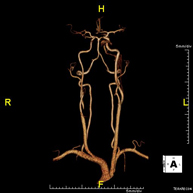

- Supra-aortic trunk MRI angiography

This non-invasive diagnostic procedure uses an electromagnetic field and radio waves (from a transmitter and receiver) to acquire high-definition anatomical images of the carotid and vertebral arteries in the neck. It is a radiation-free procedure. In most cases, paramagnetic contrast (gadolinium) is required. It enables non-invasive angiographic studies using a gadolinium injection, with subsequent 2D and 3D reconstruction using specialised workstations. Indicated for: cerebral circulatory problems, syncope.